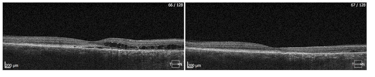

Obraz SOCT w różnych postaciach CSCR. Postać ostra charakteryzuje się wydłużeniem fotoreceptorów oraz brakiem ścieńczenia siatkówki sensorycznej. Z kolei postaci przewlekłe mogą przybierać różne formy morfologiczne: na jednym zdjęciu widoczna jest hiperrefleksyjna fibryna w płynie siatkówkowym oraz ziarnistości na granicy siatkówki sensorycznej. Z kolei drugi przykład pokazuje znaczne ubytki siatkówki sensorycznej pomimo resorpcji SRF po wykonanej SML.